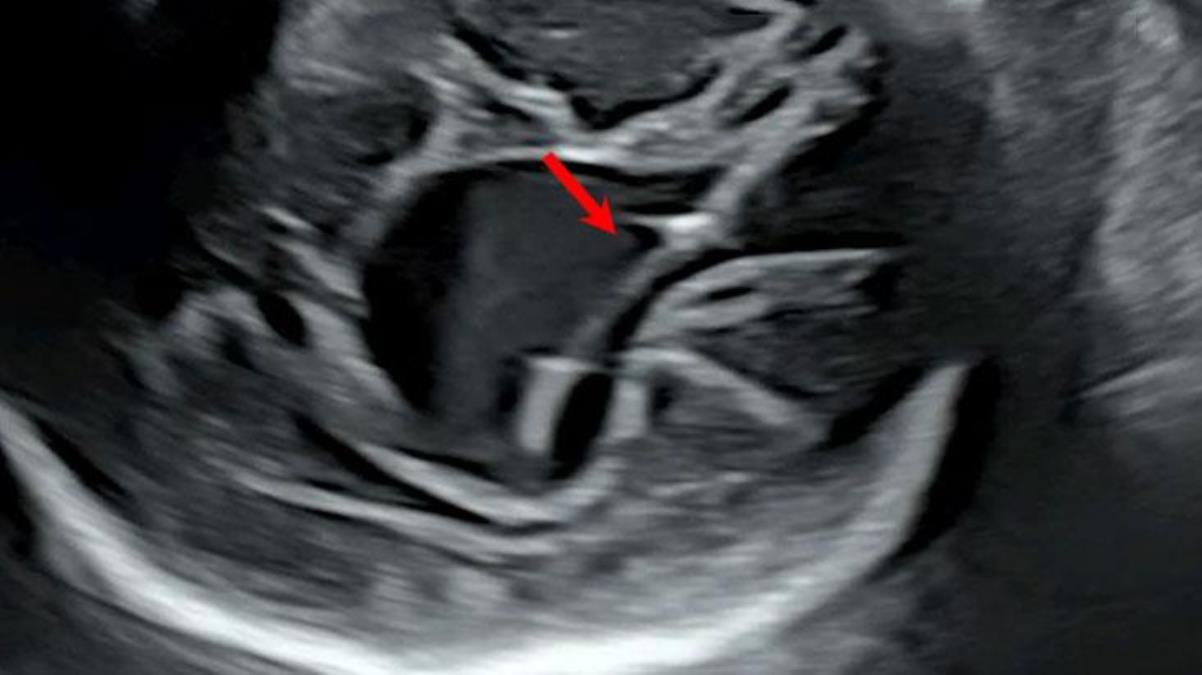

Doktorlar, “Galen ven malformasyonu” adı verilen, nadir ortaya çıkan hastalığı bebek 30 haftalıkken tespit etti. ABD’de “Stroke” adlı bilim dergisinde yayımlanan ve alanında ilk olduğu belirtilen ameliyat, ultrason kullanılarak atardamarın tespiti yöntemiyle gerçekleştirildi.

Doktorlar, annenin karnından uzun bir iğneyi bebeğin beyninin etkilendiği kısma yönlendirmek için ultrason kullandı. Doktorlar, daha sonra damarlara geri akışı engellemek amacıyla damarın içine bir madde enjekte etti. Ameliyatı başarılı şekilde gerçekleştiren doktorlar, henüz doğmamış bebeği doğumundan sonra ölümüne yol açacak şekilde kalp yetmezliği ve nörolojik rahatsızlıklar gibi ciddi hastalıkların ortaya çıkmasından kurtarmış oldu.